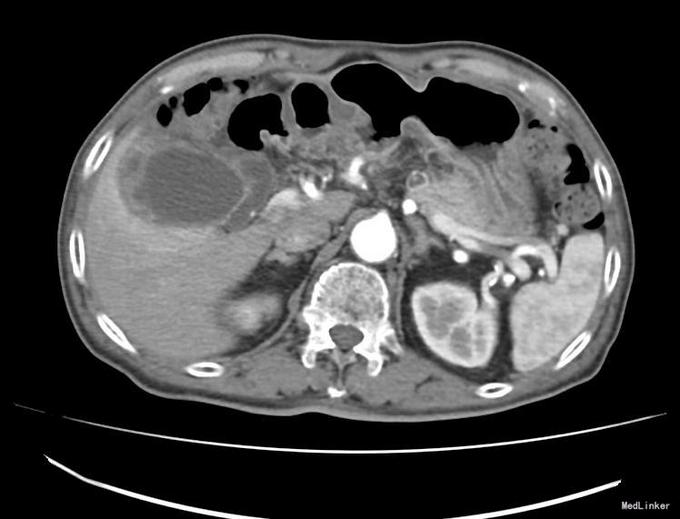

查体:右上腹轻压痛,无反跳痛、肌紧张。墨菲氏征弱阳性。 辅助检查:腹部CT:胆囊体积增大,壁增厚,以胆囊底部为著,增强扫描可见轻度强化,胆囊周围可见积液。MRI:胆囊增大,壁增厚,壁内可见多发结节状低信号灶。胆囊内可见泥沙样短T2信号影。